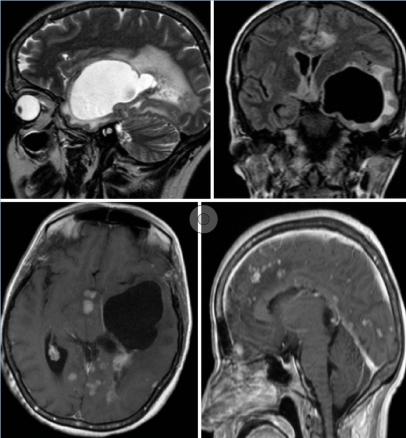

Cette femme de 44 ans avait un tableau d’hypertension intracrânienne et des troubles du comportement, un syndrome pyramidal droit, une paralysie faciale centrale droite, un syndrome confusionnel et un œdème papillaire ; pas de particularité pour le reste de l’examen, notamment pulmonaire. Le bilan biologique (test de sensibilité à la tuberculine, antigène carcinoembyonnaire, métabolisme calcique, cytologie du lavage bronchoalvéolaire) et la radiographie pulmonaire étaient normaux. La tomodensitométrie (TDM) cérébrale (fig. 1 ) montrait une lésion kystique temporale gauche exerçant un effet de masse sur la ligne médiane avec un œdème périlésionnel. Après injection il y avait une prise de contraste micronodulaire leptomeningée diffuse et de la corne occipitale du ventricule latéral gauche. L’imagerie par résonance magnétique (IRM) [fig. 2 ] montrait une volumineuse lésion kystique expansive temporale gauche, dont les parois ne se rehaussaient pas après injection du produit de contraste avec un hypersignal T2 périlésionnel ainsi qu’un engagement temporal. La résection chrirugicale et la corticothérapie permettaient une amélioration neurologique immédiate. L’histologie était en faveur d’un granulome épithéloide gigantocellulaire sans nécrose caséeuse.